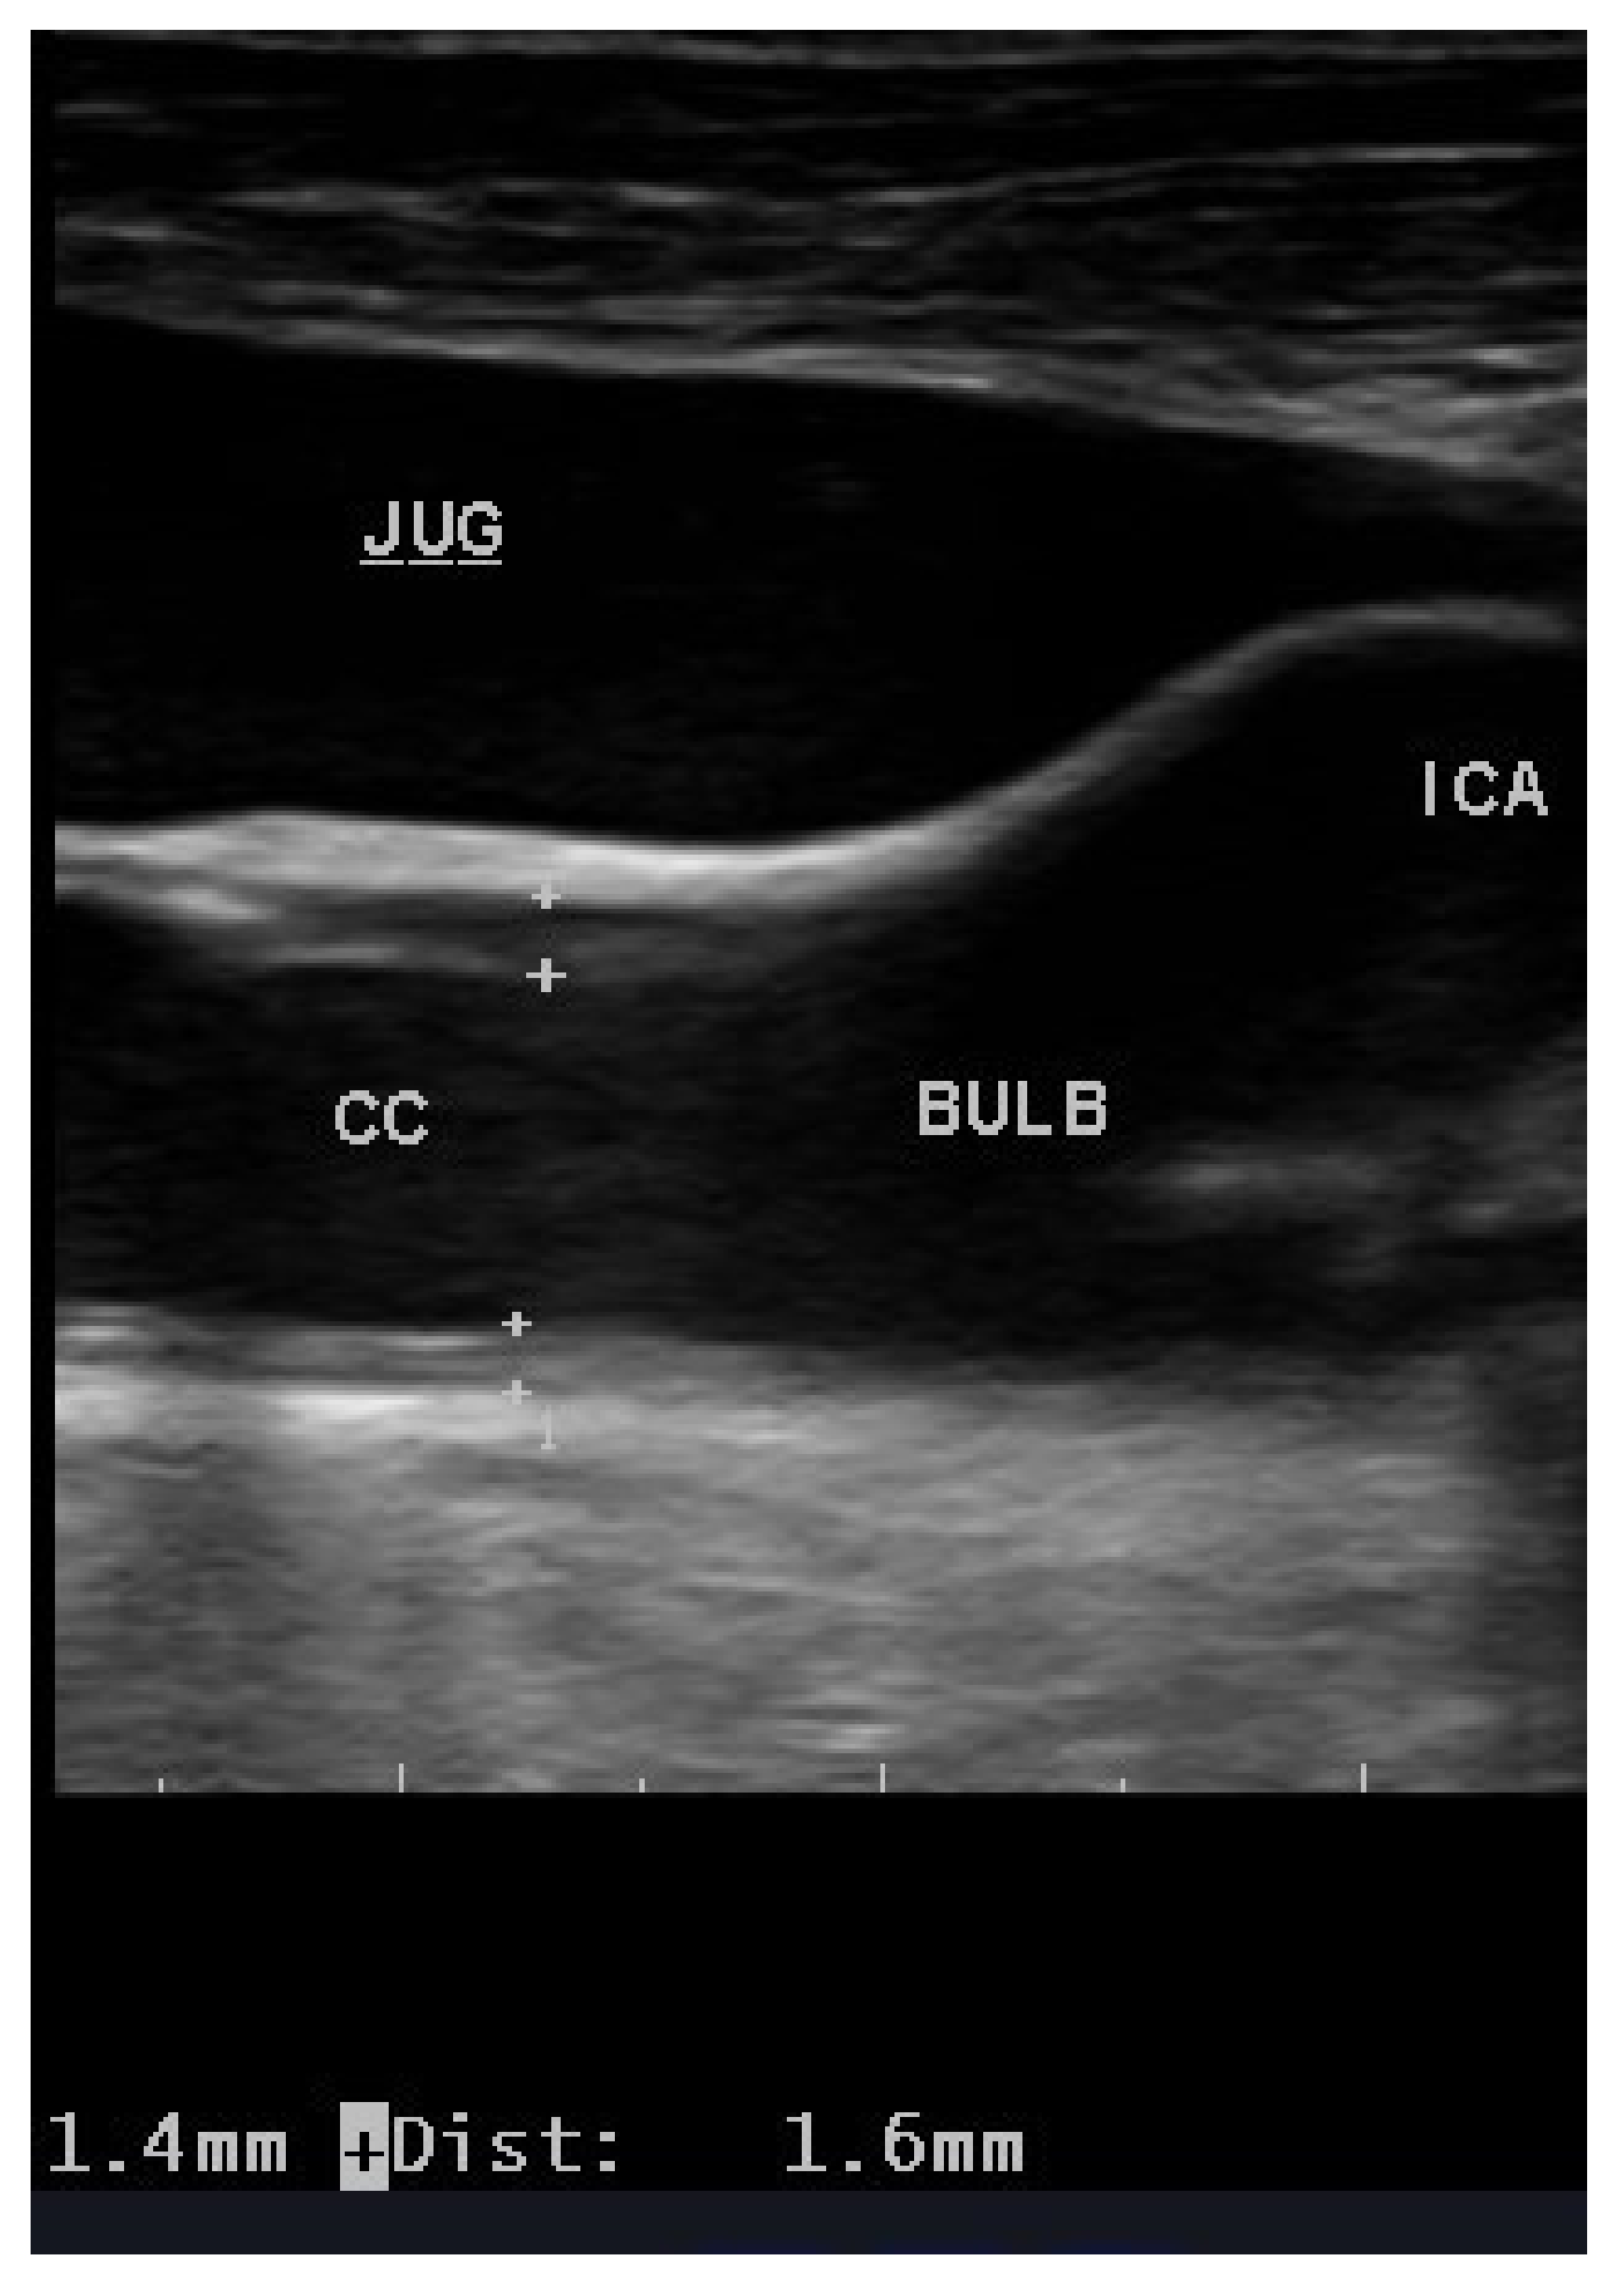

Globally, the most common method of estimating atherosclerotic load has been carotid ultrasound. This is due to the ease of access to a superficial artery, the availability of high performance and reasonably low-cost ultrasound equipment and the presence of a large body of evidence (thousands of articles) that relates carotid artery pathology to cerebrovascular and cardiovascular events. The most frequent parameter studied in the extracranial carotid is the measurement of the intima-media thickness (IMT, Figure 1), as proposed by Pignoli et al. in 1986 [24]. Measurement of the IMT quickly established itself as a valid and reliable measure, with ad hoc protocols being developed for its use in numerous studies and drug trials, including use with lipid lowering drugs [25]. However, a quality control is needed to guarantee the reliability of results reported in both epidemiological and interventional studies. A large number of studies [26,27] have used the progression of the IMT as a surrogate marker for the initial stages of atherosclerosis [28,29], and a recent meta-analysis has suggested a positive association between the progression of the IMT and cardiovascular risk [30]. Recently, the value of carotid IMT for measuring subclinical atherosclerosis has been put in doubt [31], although Sirtori has subsequently defended it [32]. The ARIC study demonstrated in 2010 that the presence of carotid plaques in addition to IMT measurement was able to improve prognostic power in the prediction of coronary heart disease [33].

Figure 1.

Increased IMT of the common carotid artery (1.4 mm far wall; 1.6 mm near wall). Legend: CC, common carotid; Bulb, carotid bulb; ICA, internal carotid artery; JUG, jugular vein.